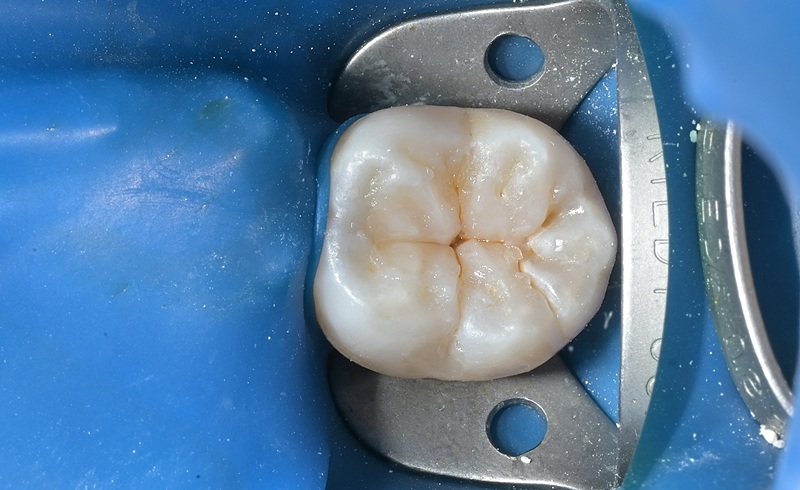

術後

| 治療名 | セラミックインレーによる虫歯の再治療症例 |

|---|---|

| 治療説明 |

過去に治療された銀歯が外れたとのことで来院されました。内部には古い接着剤の劣化と虫歯の再発が見られたため、しっかりと虫歯を除去し、セラミック製の詰め物(インレー)で再修復を行いました。 セラミックインレーは、天然歯に近い色調と自然な透明感を持っており、見た目が気になる部位にも適しています。 |

| 治療回数・期間 | 2回 |

| 副作用とリスク | ・保険診療の銀歯に比べて費用が高くなります。 ・治療直後は一時的に知覚過敏のような症状が出ることがありますが、ほとんどの場合は数日〜1週間程度で落ち着きます。 |

| 料金(税込) | 77,000円 |